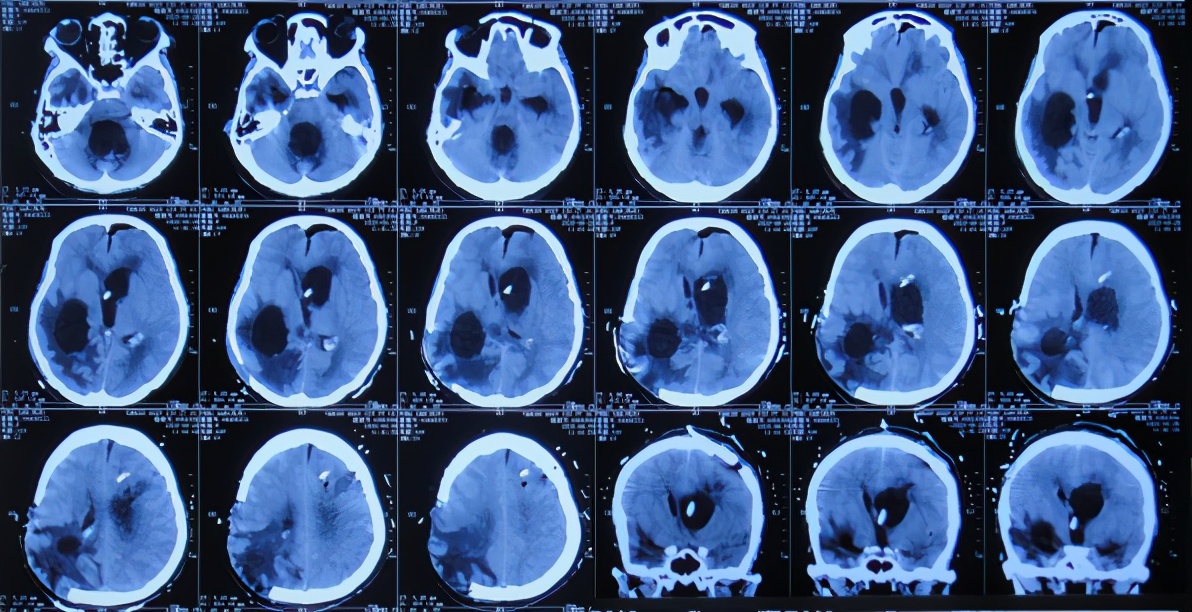

开颅术后26天2020年4月28日(腰大池引流管第4次脱出后5天),复查头颅CT发现幕上脑室系统扩张( 图-5 );但因患者症状好转,可在搀扶下独立行走,未予处理。

图-5: 2020年4月28日头颅CT

开颅术后40天2020年5月12日(腰大池引流管第4次脱出后19天),复查头颅CT示脑室持续扩大,轻度脑膨出( 图-6 )。

图-6: 2020年5月12日头颅CT

开颅术后49天2020年5月21日(腰大池引流管第4次脱出后28天),患者间断出现呕吐,骨窗脑组织膨出较前增加,复查头颅CT示脑积水脑膨出进一步加重( 图-7 )。医生建议转入上级的医院进行脑室腹腔分流术。

图-7: 2020年5月21日头颅CT